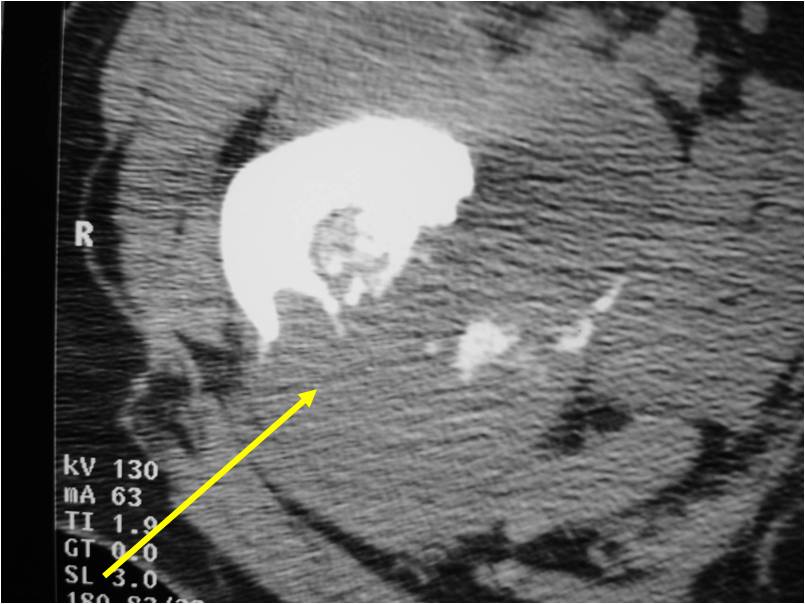

Radiology emulates pathology: Biphasic Tumor

- One region low grade chondrosarcoma

- Second more aggressive area with bone destruction, lysis of calcification, soft tissue mass

- Cortical permeation and a soft tissue mass in 70% of cases

Ill-defined, lytic intraosseous lesion

- Or extraosseous soft tissue mass

- Devoid of calcifications in continuity with lesions having the features of a cartilaginous tumor

Characteristically abrupt transition between chondroid tumor and dedifferentiated, lytic component

Bone may be expanded and adjacent cortex thickened

(Right Arrow)Aggressive Lytic Area (Dedifferentiated Sarcomatous Component) Cortical Destruction Soft Tissue Mass without Calcification